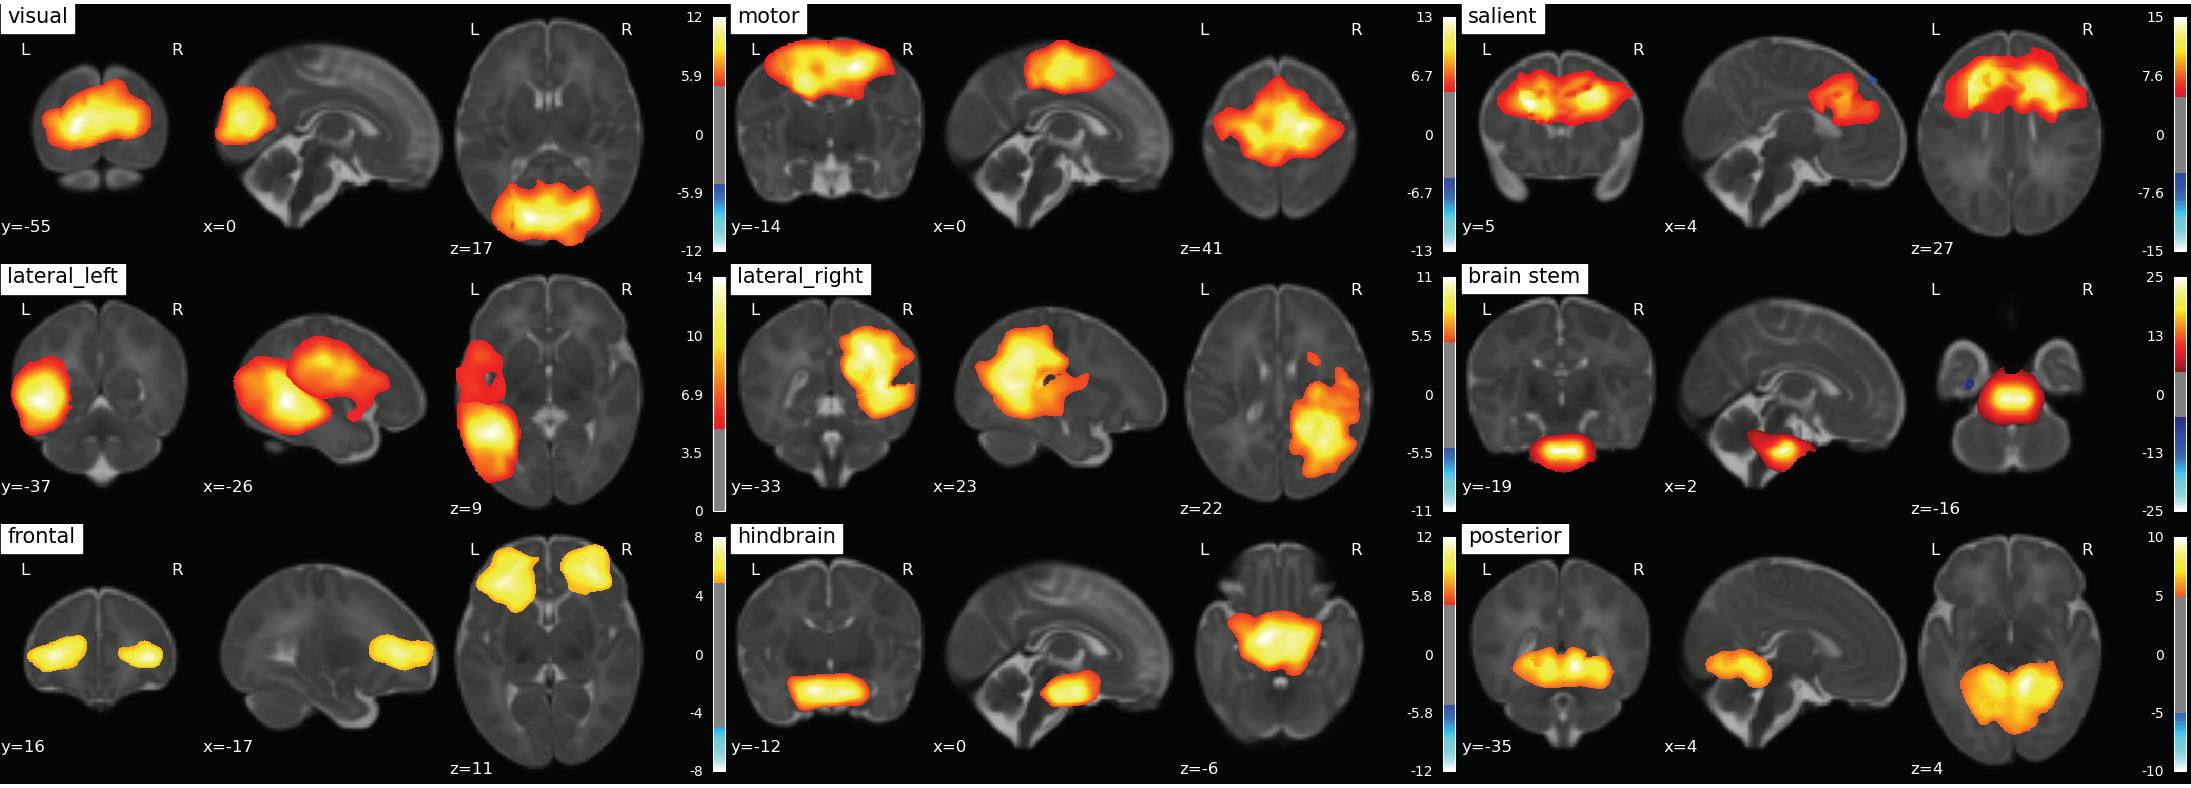

![]() |

|---|

| Fig. 1: 9 RS-networks identified from Group ICA. The lateral left network was created by combining two separate networks output from group ICA. |

307 scans of 3T fMRI data with TR=3s and ~5 minutes /100 volumes were collected from SickKids Toronto (Steven Miller). Clinical information on their sex, sedation during scan, severity of white matter injury, intraventricular hemorrhage, ventriculomegaly, cerebellar hemorrhage and stroke was provided by SickKids Toronto. After removing scans with 1) a mean frame wise displacement less than 1mm, 2) less than 98 time points, 3) subjects with stroke, and 4) scans that failed during pre-processing due to image distortion we were left with 133 scans (mean birth age 27 ± 2.5 weeks, 64 male and 69 female). Infants were born pre-term and scanned shortly after birth and again at TEA, with scan ages varying from 27 - 48 weeks. The anatomical images (T1w & T2w) were bias corrected4 and the T1w was registered to the T2w5. Anatomical and functional data was then preprocessed using the dHCP pipelines,6,7 and a study specific FIX training file was made8,9,10,11. The data was smoothed12 with a 5mm FWHM kernel and intensity normalised. Each scan was registered to the 40w template from the dHCP pipeline and group ICA13 was performed on both pre-term and TEA scans together producing 9 resting state networks (Fig. 1). The Hurst exponent was calculated using Welch’s method (reference) on the pre-processed data (Fig. 2). The mean H value was calculated in the grey matter masks output from the dHCP anatomical pipeline and in resting state networks (Fig. 3) that were created from group ICA. A Linear Mixed Effects model was used to evaluate how significant the differences of the mean H value in these 10 regions of interest were between early and at TEA scans.